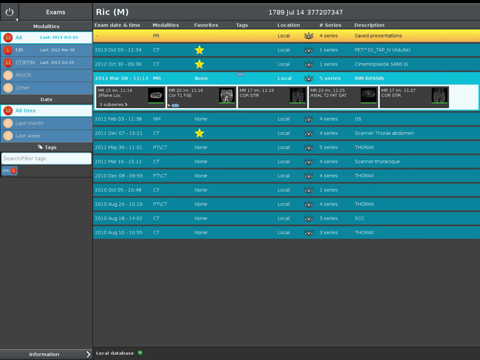

The Anywhere Streaming is now available as a free download on Apple Store for both iPhone and iPad owners.The application is supporting English language. It weighs in at a hefty 450560, so make sure you have plenty of free space on your iOS device. The new Anywhere Streaming app version 2.6.0 has been updated on 2016-04-24.

Anywhere Streaming is a DICOM visualization client that connects to Anywhere Server. It provide standard medical image navigation tools surch as : slicing, windowing, MPR, 3D VR, MIP, oblique ... All standard medical image modalities are ...